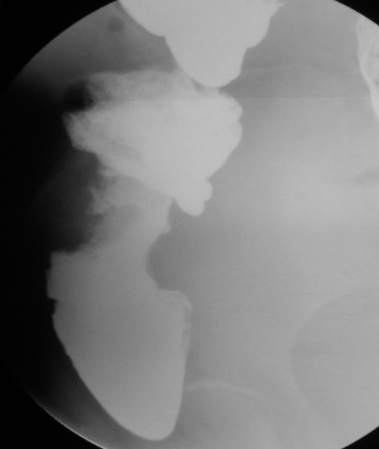

67岁女性,腹痛、腹胀半月余。查:右侧腹部有触痛,可触及肿物。

支持升结肠肿瘤性病变。

常规考虑---结肠癌,不排除诱发肠套叠了。

支持升结肠癌。

支持考虑升结肠癌。

谢谢大家讨论。与x6045完全不同。本例手术结果为右侧结肠旁沟及盆腔多发脓肿。术后病人恢复良好,现已出院。

手术见结肠旁沟及盆腔多发脓肿。

感谢楼主反馈结果!造影见果核征,首先考虑肿瘤,即使误诊也应该这样考虑。